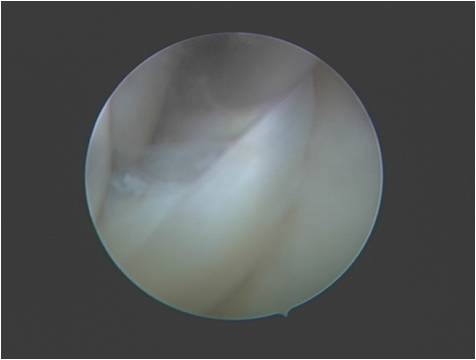

半月板缝合